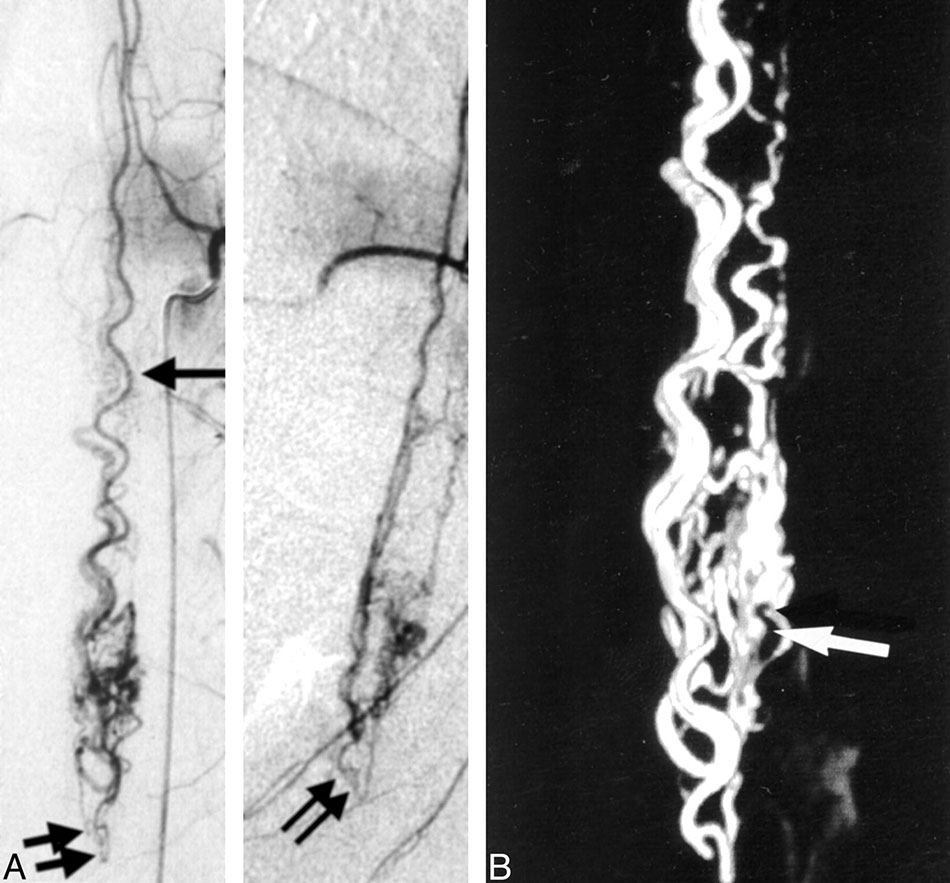

A diagnostic spinal angiography is a medical procedure that offers an extremely precise evaluation of the blood vessels surrounding the spinal cord.

Spinal angiography helps diagnosing medical conditions that involve the arteries and veins of the spinal cord. This typically includes spinal cord vascular malformations, such as dural arteriovenous fistulas (DAVF) and arteriovenous malformations (AVM), but also certain types of spinal cord stroke and disorders involving the spinal cord venous system, such as spinal venous thrombosis

Dural arteriovenous fistulae (AVF) are blood vessels that represent abnormal connections between arteries and veins that are found in the covering of the brain. This covering is known as the dura, hence the name. There is a direct connection between the arteries and the vein without any vessels between.

These fistulae or abnormal connections usually develop over time and can occur after trauma, infection or thrombosis (clotting-off) of veins in the dura. The fistula may cause abnormal noises in the head due to the high flow of blood. They can also cause headaches or result in bleeding into the brain.

The treatment is similar to those available for AVMs and can include embolization, surgery, and in some cases radiosurgery. Embolization is often used as the primary therapy to treat this problem. Embolization is performed by placing a tiny catheter directly into the AVF. Embolic material is then injected into the blood vessel to block them up. The embolic material leaves the catheter as liquid and solidifies within the AVF blood vessel to block it up. Sometimes coils are also used to block up the AVF.